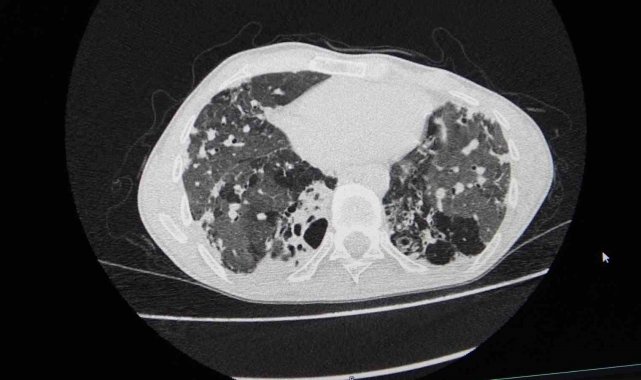

Göğüs Cerrahisi Uzmanı Prof. Dr. Ahmet Erdal Taşçı, akciğer nakli bekleyen hastanın yıllardır bronşektazi hastalığıyla mücadele ettiğini belirterek, "Hastamızın yaşaması için tek çare nakildi. Nakil başarılı geçti. Bu operasyon, bizim ekibimiz için teknik anlamda standart bir akciğer nakliydi. Ancak dikkat çeken nokta, aynı anda hastanemizde bir karaciğer nakli operasyonunun da gerçekleştirilmiş olmasıydı. Aynı bağışçının organları, iki ayrı hastaya; biri akciğer, diğeri karaciğer olarak nakledildi. Bu vesileyle bağışçımıza Allah'tan rahmet, yakınlarına da sabır diliyoruz. Böylesine acılı bir anda başkasının hayatına dokunabilmek, örnek bir davranış" dedi.

"Organ nakli, bir ülkenin sağlık sisteminin ne kadar gelişmiş olduğunu gösteren önemli bir göstergedir." diyen Taşçı, "Ameliyatı gerçekleştirilen hastamız, yoğun bakımda uyanık ve solunum desteğiyle izleniyor. Kısa sürede yeni akciğerleriyle nefes alması bekleniyor" diye konuştu. Taşçı, "Türkiye'de özellikle kadavra donör organ bağışlarının artması büyük önem taşıyor. Herkesin bir gün kendisinin veya sevdiklerinin de bu ihtiyaca düşebileceğini düşünerek, organ bağışı konusunda daha duyarlı ve bilinçli hareket etmesi gerekiyor. Ülkemizde Sağlık Bakanlığı'nın bu alandaki organizasyonu ve altyapısı gerçekten çok iyi seviyede. Bu anlamda emeği geçen herkese teşekkür ediyoruz" ifadelerini kullandı.